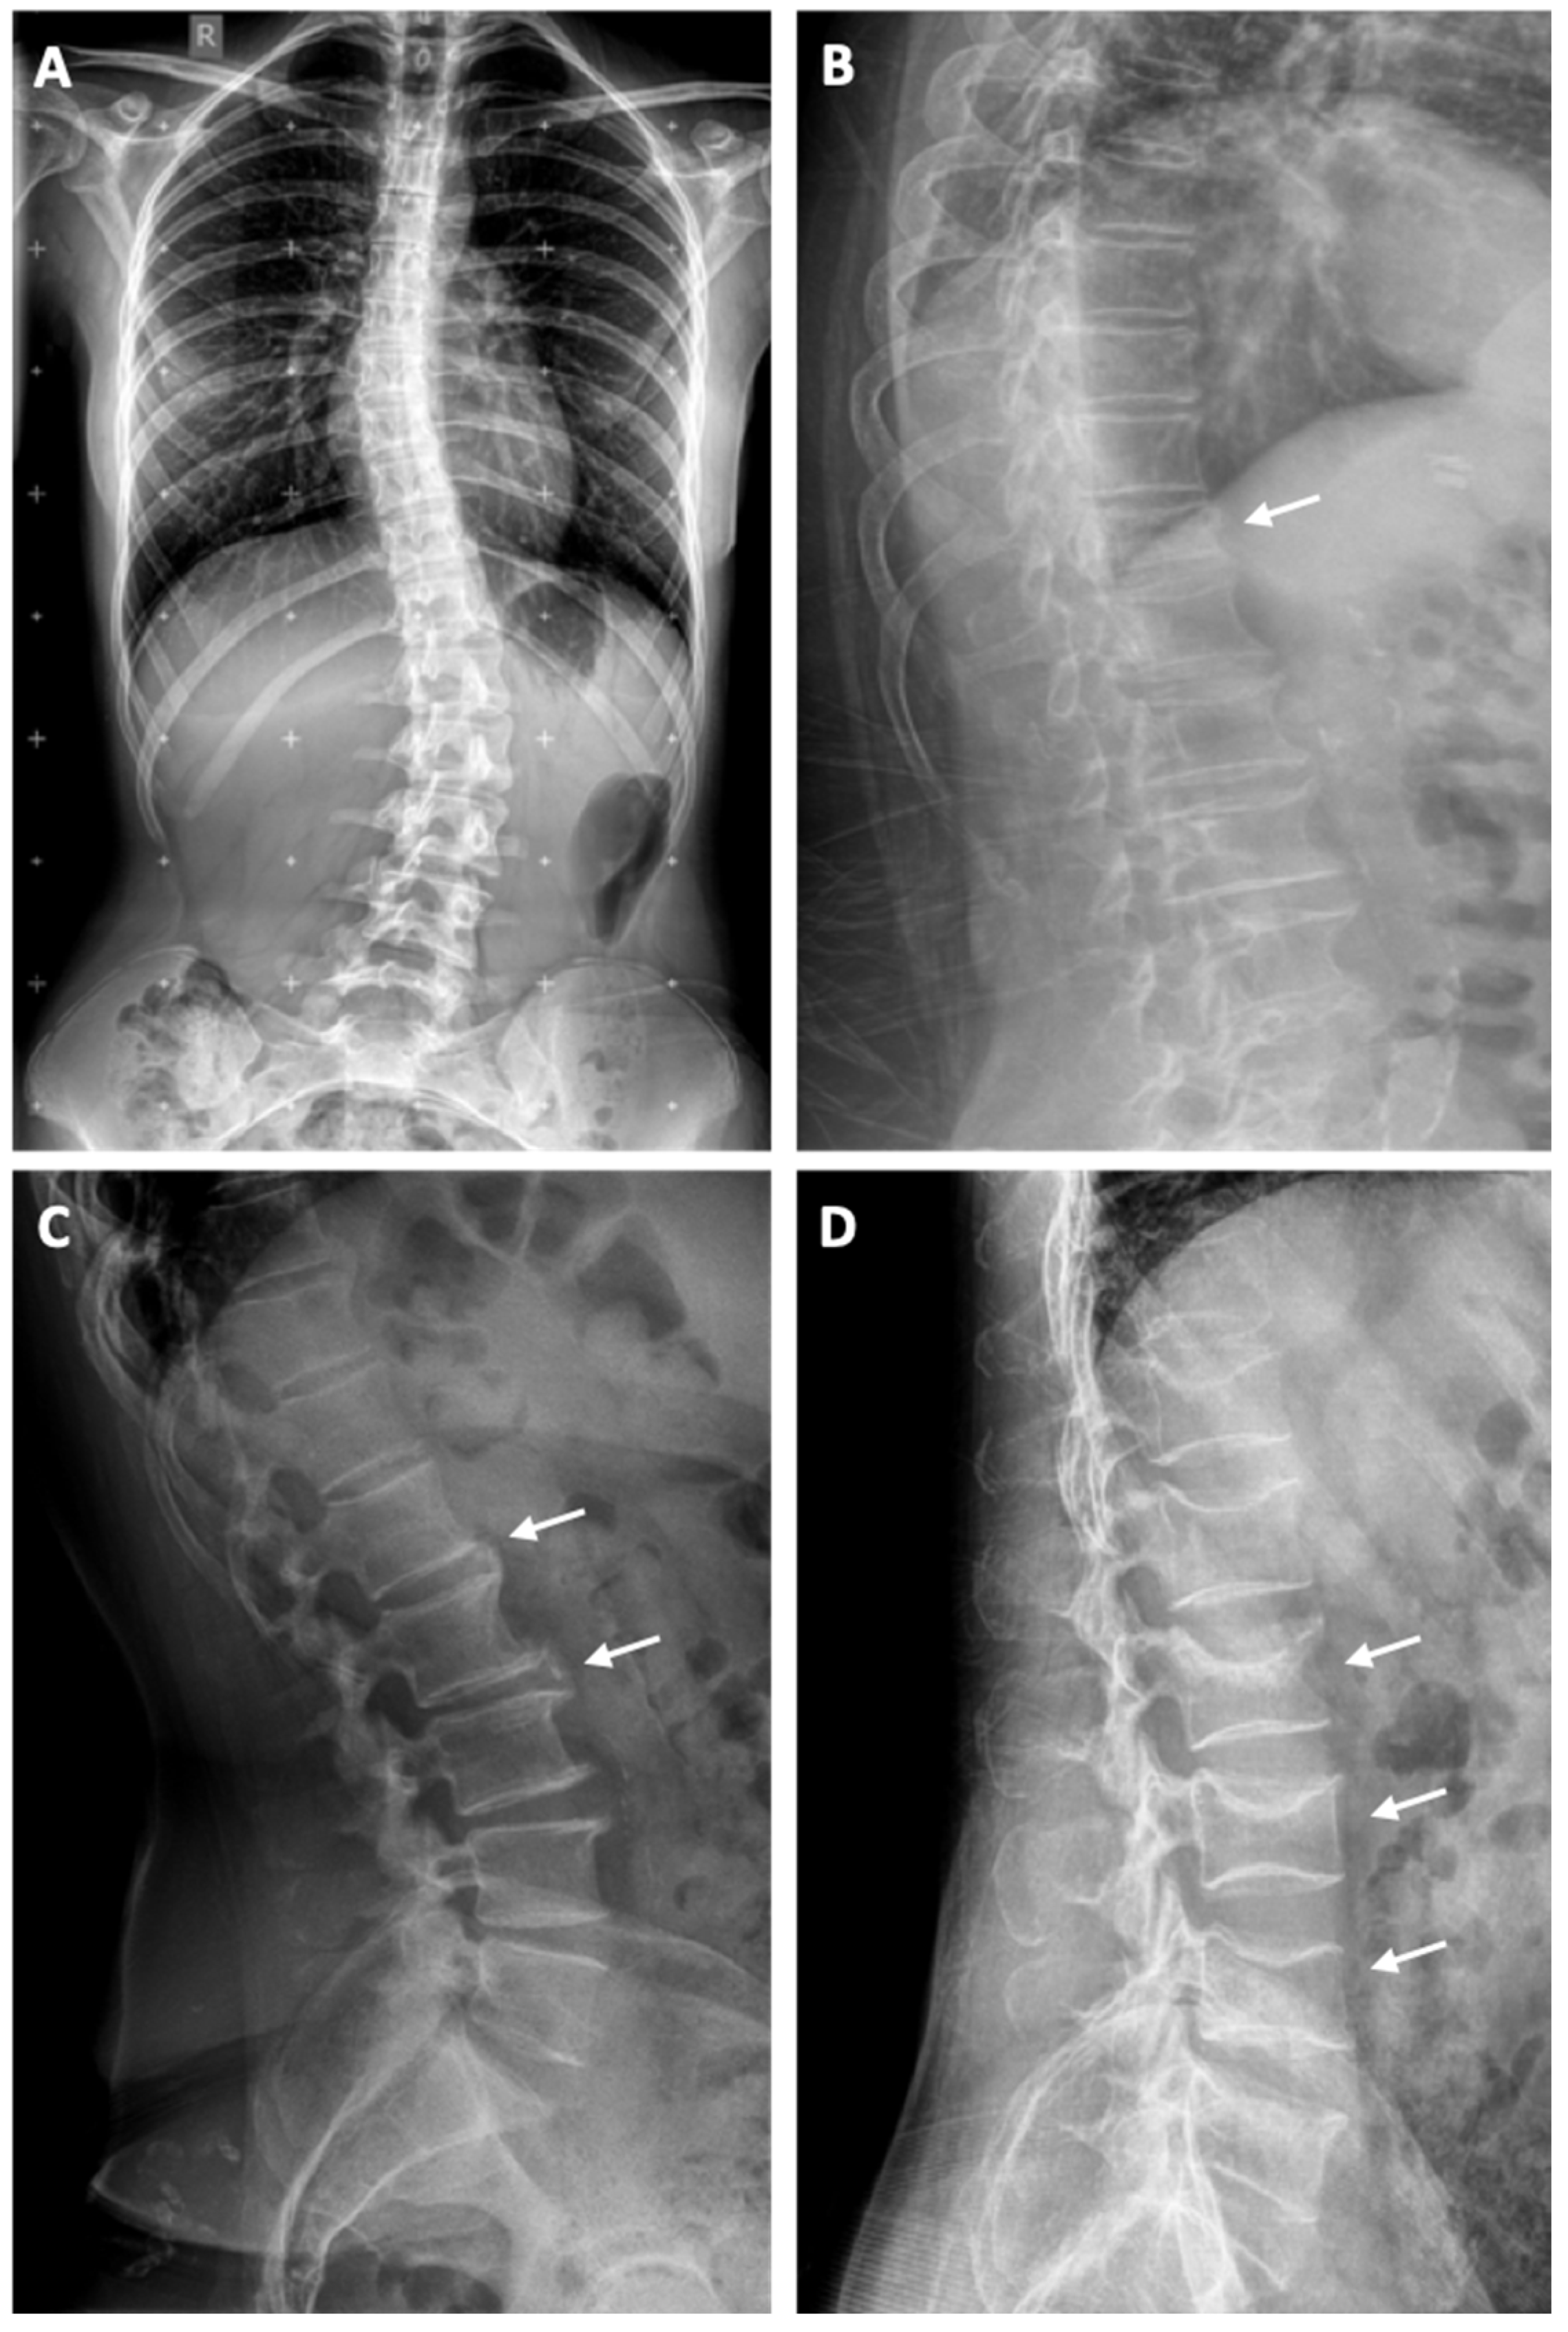

3.1. Scoliosis